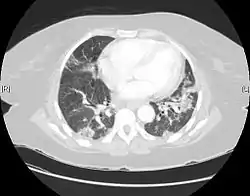

![]() منظر لالتهاب الرئة الخلالي المعتاد تحت الأشعة المقطعية. تليف منخر يظهر في كلتي الرئتين. منظر لالتهاب الرئة الخلالي المعتاد تحت الأشعة المقطعية. تليف منخر يظهر في كلتي الرئتين. | |